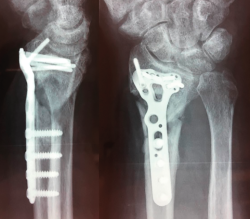

Figura 4. Aspecto final al mes de la retirada del material.

El paciente requirió extracción de la placa por tenosinovitis de los flexores al año de la segunda cirugía (Figura 4). La exploración final, al mes de la retirada del material, comprobó un balance activo de los arcos de movimiento: extensión 40°, flexión 60°, desviación radial 20°, desviación cubital 40° y pronosupinación completa. Balance muscular de 4/5, cierre completo del puño y pinza oposición completa.